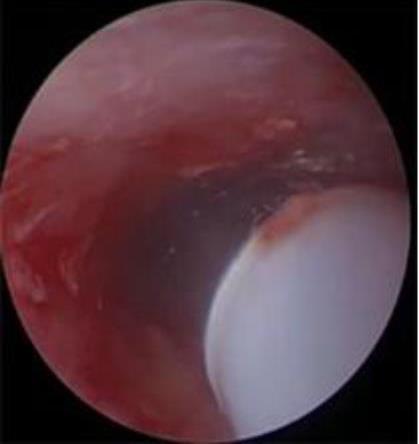

摘要:目的 分析医用生物蛋白胶应用于耳内镜下鼓膜修补术的临床疗效。方法 回顾性分析2022年10月-2023年10月该院收治的60例单纯鼓膜穿孔患者的临床资料,根据手术方法不同,将患者分为研究组和对照组,各30例。研究组术中使用医用生物蛋白胶粘合残余鼓膜和修补材料;对照组术中采用明胶海绵覆盖修补鼓膜。观察两组患者术后的鼓膜愈合情况(鼓膜愈合率、愈合时间、干耳时间和外耳道上下径)和并发症发生情况;于手术前后,采用纯音测听法(500、1 000、2 000、4 000 Hz),测量两组患者气导阈值,观察听力改善程度;采用视觉模拟评分法(VAS)评分,评估患者术后疼痛程度。结果 两组患者术后鼓膜愈合率、愈合时间、外耳道上下径和并发症发生率比较,差异均无统计学意义(P > 0.05)。研究组术后平均气导听阈明显低于对照组,差异有统计学意义(P < 0.05)。研究组术后干耳时间短于对照组,术后第1天疼痛VAS评分明显低于对照组,差异均有统计学意义(P < 0.05)。结论 医用生物蛋白胶应用于耳内镜下鼓膜修补术,可有效地降低气导听阈,缩短干耳时间,减轻患者疼痛,且不增加并发症发生率,值得临床推广应用。